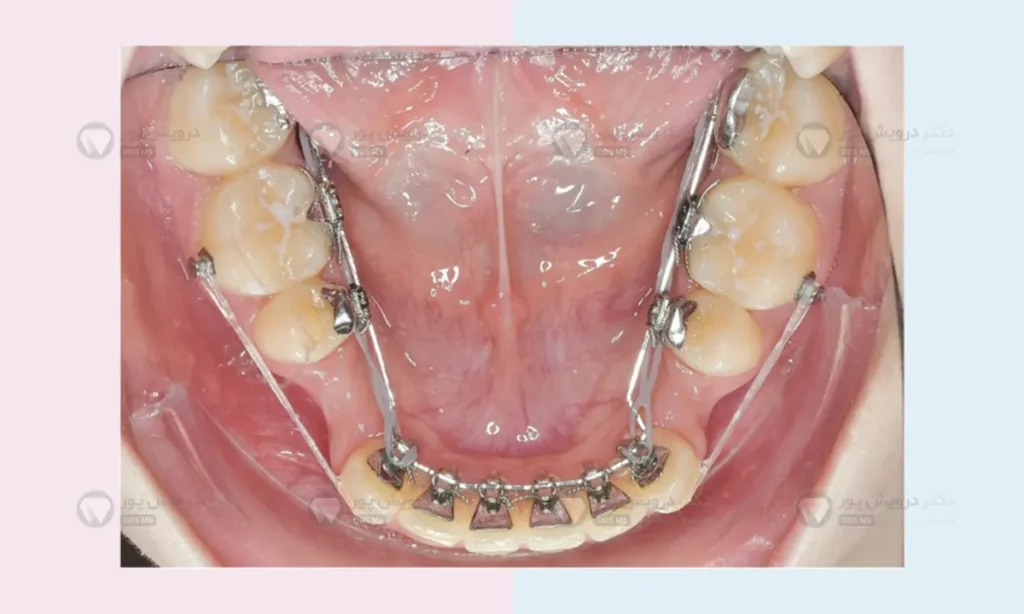

برای این کار از دستگاه هایی مانند “هدگیر” (در گذشته)، “پندولوم” یا روش های مدرن تری مانند استفاده از “مینی اسکرو” (TADs) استفاده می شود. مینی اسکروها پیچ های بسیار کوچکی هستند که در استخوان فک قرار داده می شوند و به عنوان یک لنگرگاه بسیار قوی عمل می کنند تا بتوان دندان های آسیاب را بدون حرکت ناخواسته سایر دندان ها، به عقب راند.